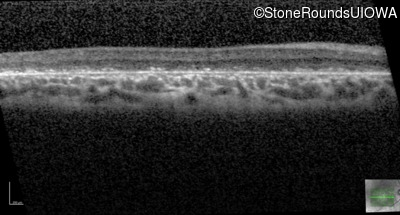

Optical Coherence Tomography - Left - 10/160 -1

Exemplar / OCT Stack